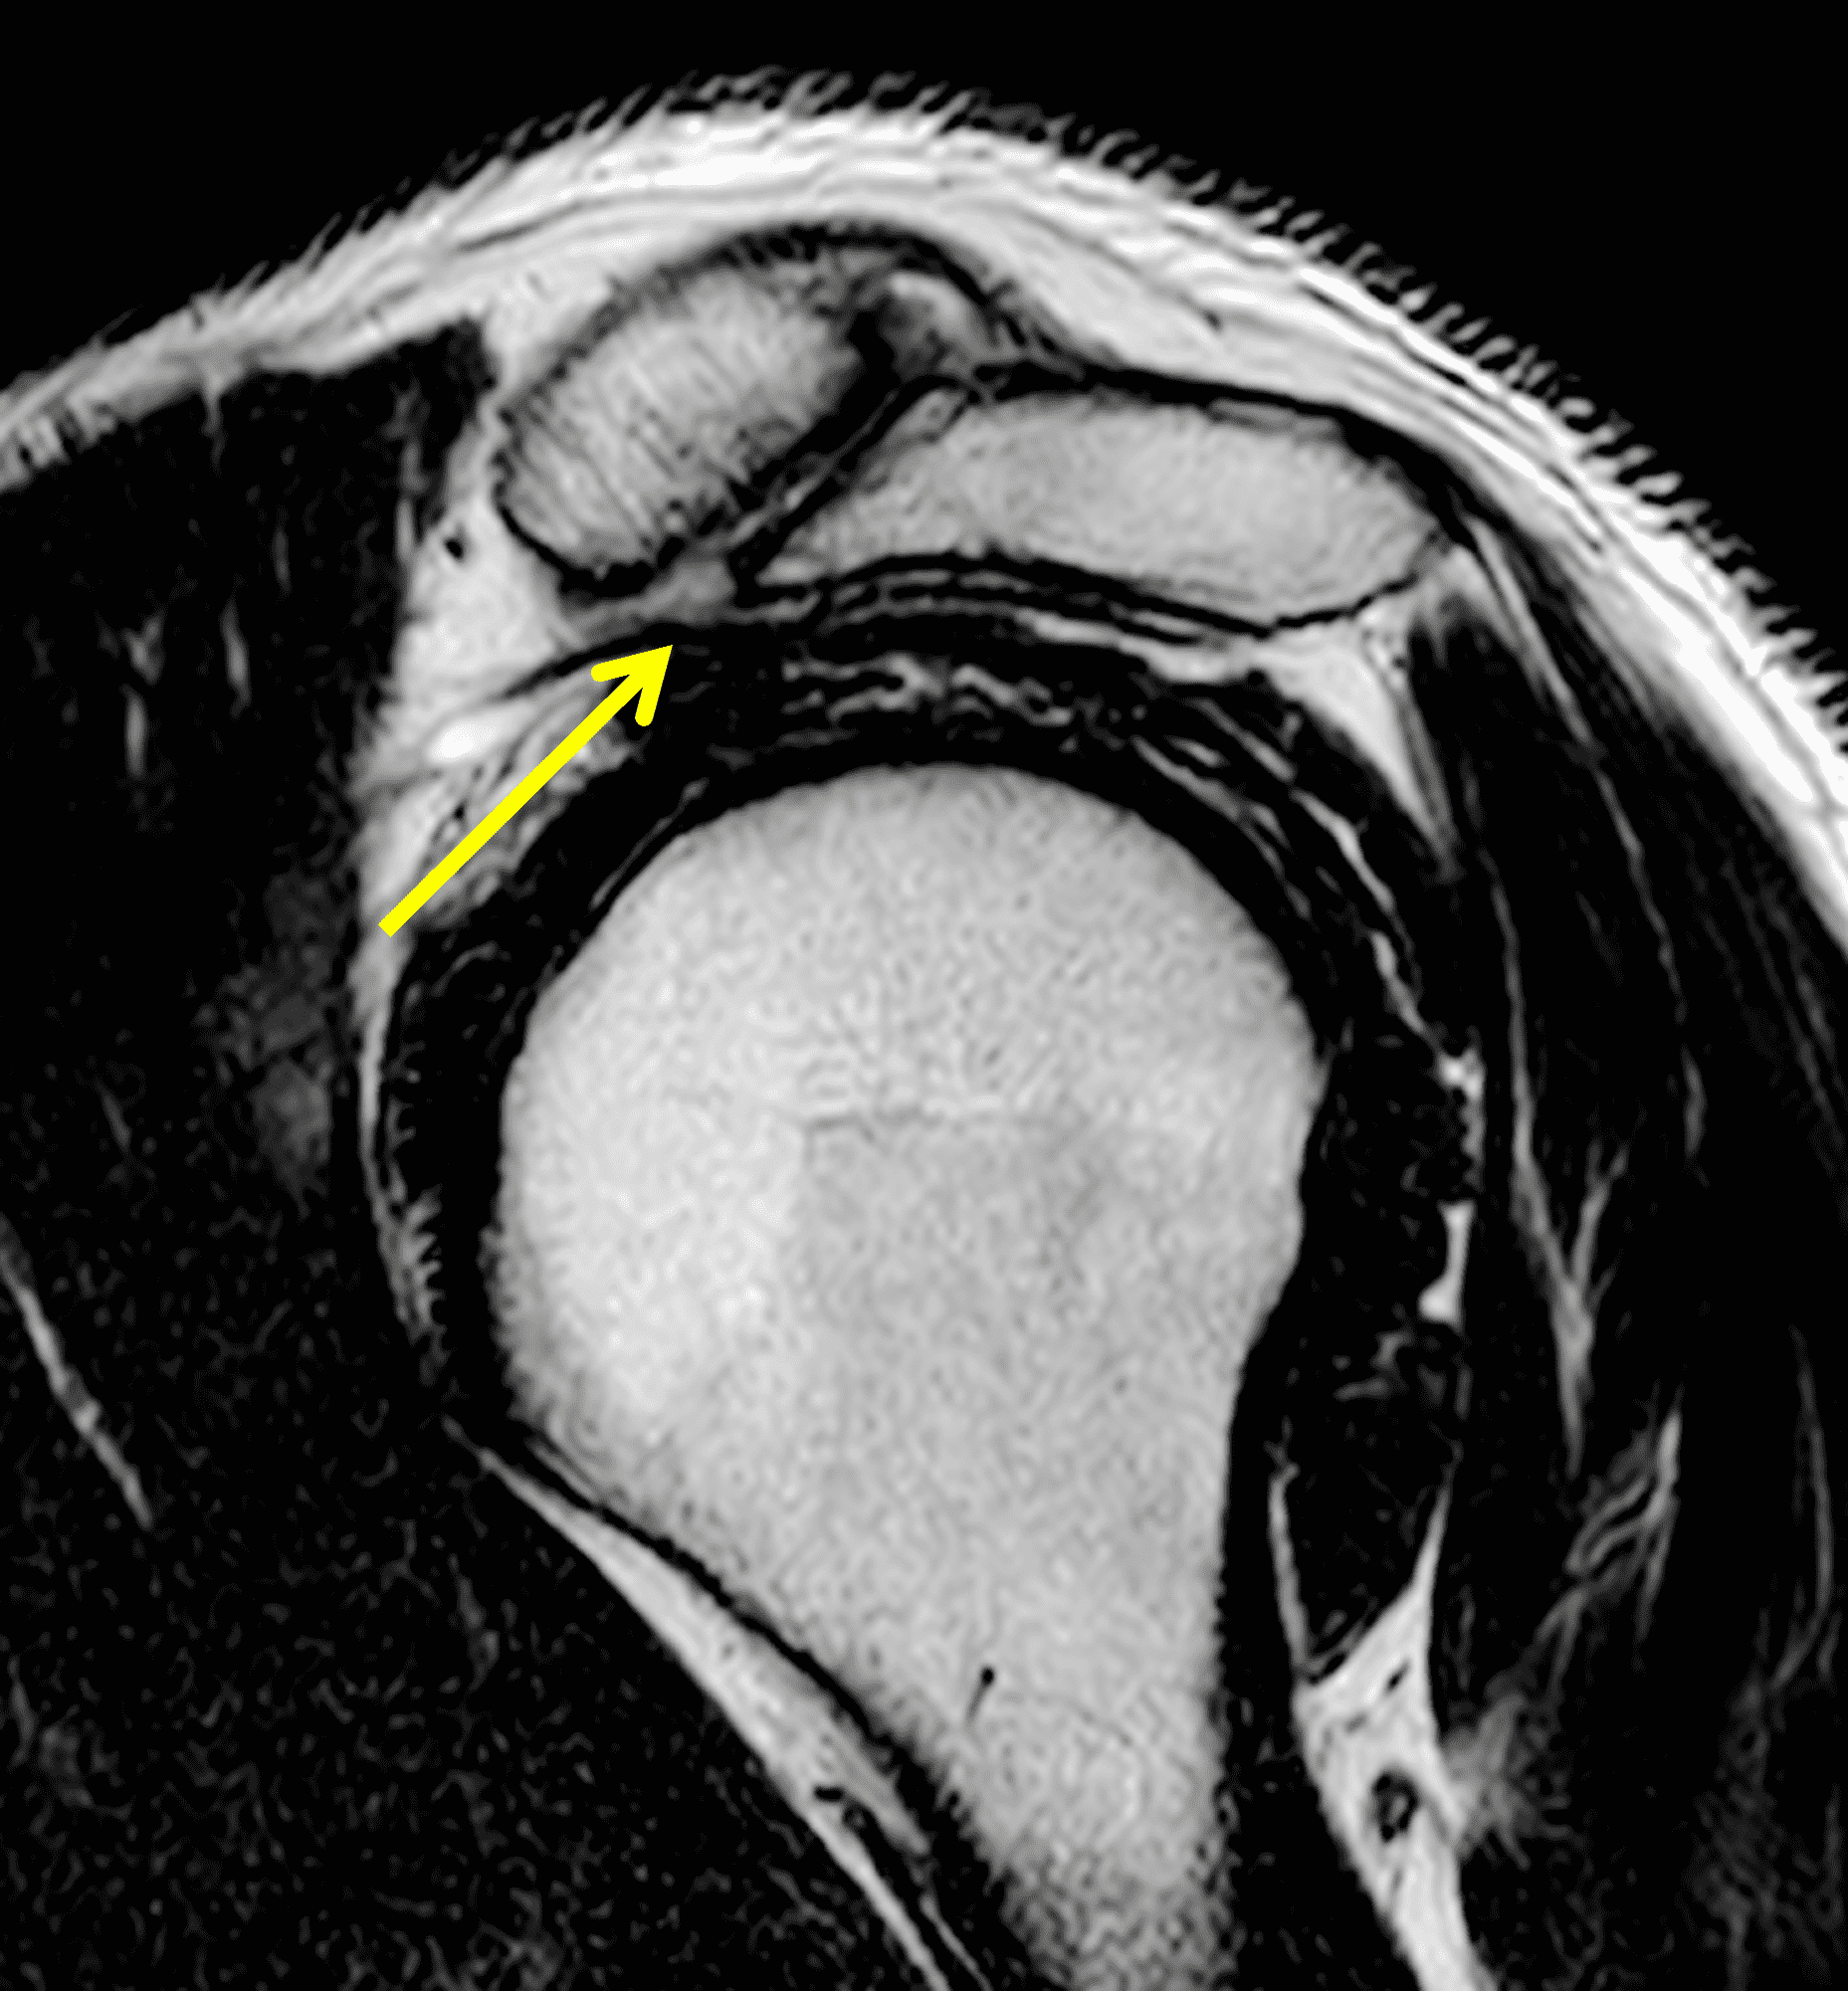

A 49-year-old male, avid weightlifter complains of chronic pain along the superior aspect of his right shoulder. He denies acute trauma. An AP radiograph (Figure 1A), as well as oblique coronal SPAIR (Figure 1B), axial fat-suppressed fluid sensitive (Figure 1C), and oblique sagittal T2-weighted images (Figure 1D) are shown. What are the findings? What is your diagnosis?

MRI: MRI is the primary imaging modality used for the diagnosis of DCO and identifies relevant findings earlier than radiographs or CT.  To differentiate DCO from similar conditions, it is important to identify underlying findings that are isolated to or more pronounced in the distal clavicle compared to other structures.  Osseous changes along both the acromial and distal clavicular margins of the joint often point to a different diagnosis.2

The principle MRI finding of DCO is distal clavicular marrow edema and surrounding inflammation on fluid-sensitive pulse sequences, especially with fat suppression (Figures 3 and 4).2, 9 Marrow changes can occur in patients with normal radiographs,10 in which case a term like “stress/overuse related marrow edema,” might be preferable to “osteolysis.” On MRI, more severe cases may show erosions or cysts in the distal clavicle and loss of the subchondral bone plate in addition to more pronounced marrow and soft tissue edema. A band of low signal paralleling the distal bone end may be present, suggesting a stress fracture line (Figure 5).8 However, a similar appearance can be due to the sclerotic rim surrounding distal clavicle cysts or small erosions (Figure 6). A small effusion or mild synovitis is often present in the AC joint.  Soft tissue edema within and surrounding the AC joint capsule and distal clavicular periosteum may be visible (Figure 3).  Some patients may also show marrow edema (or even erosions) in the anterior acromion, but the changes are typically more severe in the distal clavicle (Figures 5 and 7).2